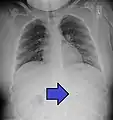

عملة نقدية تظهر في أشعة للصدر